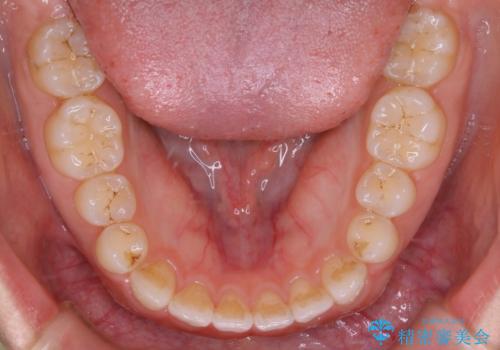

- マウスピース(インビザライン)

- 治療期間

- 1年6ヶ月

すきっ歯と噛み合わせの治療をしたいとのことで、インビザラインを用いて矯正治療を行うこととなりました。

すきっ歯の場合、ガタつきを治したりするのに必要なスペースが最初から空いているため、そのスペースを利用して比較的短期間で効率よく治療を進めることが可能となります。